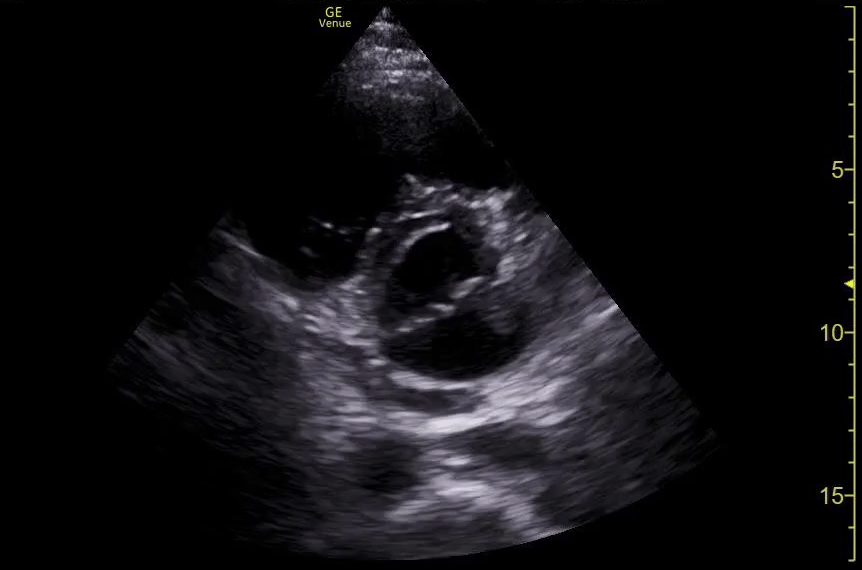

Pericardial and Pleural Effusions

Pericardial Effusion

Pacer Lead Migration

Mitral Valve Prolapse

Left Atrial Mass

Complete Heart Block

Atrial Flutter

Supine vs Left Lateral Decubitus

Normal 4 View Echo